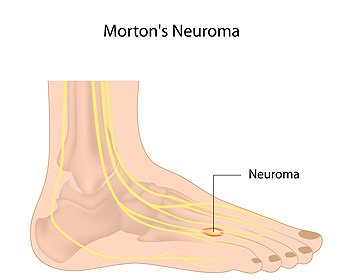

Symptoms of Morton’s Neuroma

The place on the foot where pain from Morton’s neuroma is typically felt is the bottom of the third and fourth toes. This condition can develop as a result of a swollen nerve in the ball of the foot. Some of the symptoms that patients may experience can include numbness or a tingling sensation, a burning pain, or a feeling that something is inside the bottom of the foot. There are, however, some methods that can be implemented which may help in finding mild relief. These may include performing exercises to aid in strengthening and stretching the foot, in addition to massage therapy. Patients may also find comfort in resting the foot, or wearing shoes that have adequate room for the toes to move freely. If you have any kind of pain in your foot, it is suggested that you speak to a podiatrist who can properly diagnose and treat the cause.

The place on the foot where pain from Morton’s neuroma is typically felt is the bottom of the third and fourth toes. This condition can develop as a result of a swollen nerve in the ball of the foot. Some of the symptoms that patients may experience can include numbness or a tingling sensation, a burning pain, or a feeling that something is inside the bottom of the foot. There are, however, some methods that can be implemented which may help in finding mild relief. These may include performing exercises to aid in strengthening and stretching the foot, in addition to massage therapy. Patients may also find comfort in resting the foot, or wearing shoes that have adequate room for the toes to move freely. If you have any kind of pain in your foot, it is suggested that you speak to a podiatrist who can properly diagnose and treat the cause.

Morton’s neuroma is a very uncomfortable condition to live with. If you think you have Morton’s neuroma, contact one of our podiatrists of James Kutchback, DPM, CWS-P. Our doctors will attend to all of your foot care needs and answer any of your related questions.

Morton’s Neuroma

Morton's neuroma is a painful foot condition that commonly affects the areas between the second and third or third and fourth toe, although other areas of the foot are also susceptible. Morton’s neuroma is caused by an inflamed nerve in the foot that is being squeezed and aggravated by surrounding bones.

Morton’s neuroma is a very treatable condition. Orthotics and shoe inserts can often be used to alleviate the pain on the forefront of the feet. In more severe cases, corticosteroids can also be prescribed. In order to figure out the best treatment for your neuroma, it’s recommended to seek the care of a podiatrist who can diagnose your condition and provide different treatment options.

Morton's Neuroma

A neuroma is a thickening of nerve tissue and can develop throughout the body. In the foot, the most common neuroma is a Morton’s neuroma; this typically forms between the third and fourth toes. The thickening of the nerve is typically caused by compression and irritation of the nerve; this thickening can in turn cause enlargement and, in some cases, nerve damage.

Neuromas can be caused by anything that causes compression or irritation of the nerve. A common cause is wearing shoes with tapered toe boxes or high heels that force the toes into the toe boxes. Physical activities that involve repeated pressure to the foot, such as running or basketball, can also create neuromas. Those with foot deformities, such as bunions, hammertoes, or flatfeet, are more likely to develop the condition.

Symptoms of Morton’s neuroma include tingling, burning, numbness, pain, and the feeling that either something is inside the ball of the foot or that something in one’s shoe or sock is bunched up. Symptoms typically begin gradually and can even go away temporarily by removing one’s shoes or massaging the foot. An increase in the intensity of symptoms correlates with the increasing growth of the neuroma.

Treatment for Morton’s neuroma can vary between patients and the severity of the condition. For mild to moderate cases, padding, icing, orthotics, activity modifications, shoe modifications, medications, and injection therapy may be suggested or prescribed. Patients who have not responded successfully to less invasive treatments may require surgery to properly treat their condition. The severity of your condition will determine the procedure performed and the length of recovery afterwards.